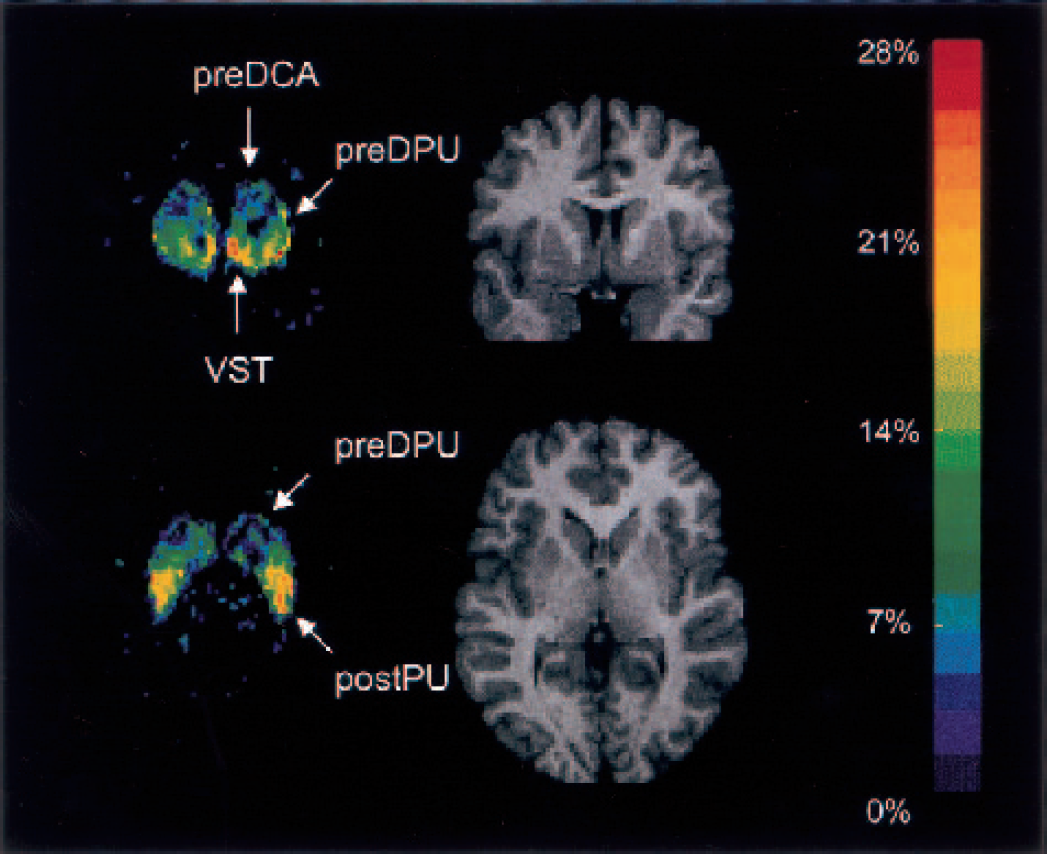

Coronal and transaxial views of the ΔV3″ map normalized to the Montreal Neurological Institute T1-template magnetic resonance imaging (MRI) scan. The images represent the voxel-based average ΔV3″ across subjects. The color scale was coded to represent the percent decrease in V3″ after amphetamine, from dark blue (0%) to red (−28%). For visual clarity, only voxels in which baseline V3″ exceeded 1 are shown. The equivalent planes from one subject's normalized MRI scan are shown for comparison. These views illustrate the two locations of highest amphetamine effect. The coronal plane, at the level of the anterior striatum, shows high displacement in the VST, low displacement in the pre-DCA, and intermediate values in the pre-DPU. The transaxial view illustrates the second area of high displacement in the post-PU, and the rostrocaudal gradient of displacement in the putamen. Pre-DCA, precommissural dorsal caudate; pre-DPU, precommisural dorsal putamen; VST, ventral striatum; post-CA, postcommissural caudate; post-PU, postcommissural putamen.

Figure 6 shows the